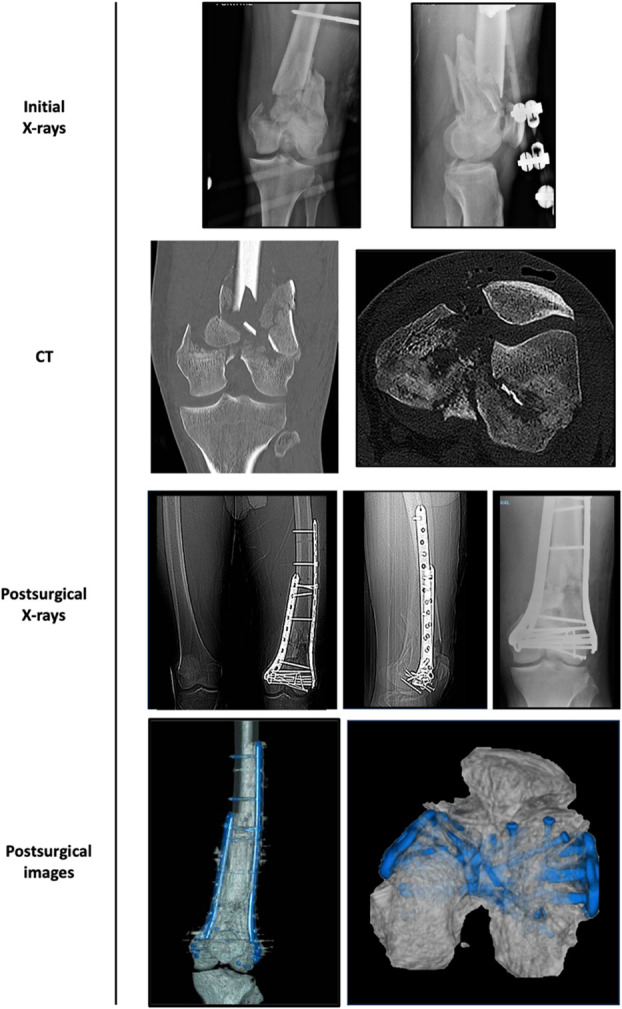

Introduction: Lateral locking plates are commonly employed for the fixation of distal femur fractures. However, scenarios involving medial comminution, extremely distal fractures, periprosthetic fractures, or nonunion could necessitate medial augmentation. This study explores the possibility of using lateral distal femoral locking plate systems for medial fixation by employing the contralateral plate.

Methods: This study presents a technical note on the application of lateral distal femur locking systems for medial augmentation in patients as indicated by current literature findings. Postoperative imaging modalities, including radiography and computed tomography (CT), were used to assess the plates' fit to the distal femur. Three cases following the specified technical note are presented.

Results: The various plate systems, all comprising distal femur locking systems, demonstrated adaptability to the medial femur anatomy as confirmed by intraoperative visualization and postoperative radiographs, including two-dimensional and three-dimensional CT scans. It has also been possible to achieve at least 3 independent fixation points regardless of the size of the medial condyle.

Conclusions: Locking distal femoral plates can be a viable option for medial augmentation in indicated cases, achieving anatomical adaptation to the distal femur. This provides robust augmentation without the need for additional instruments beyond those used for the lateral cortex.